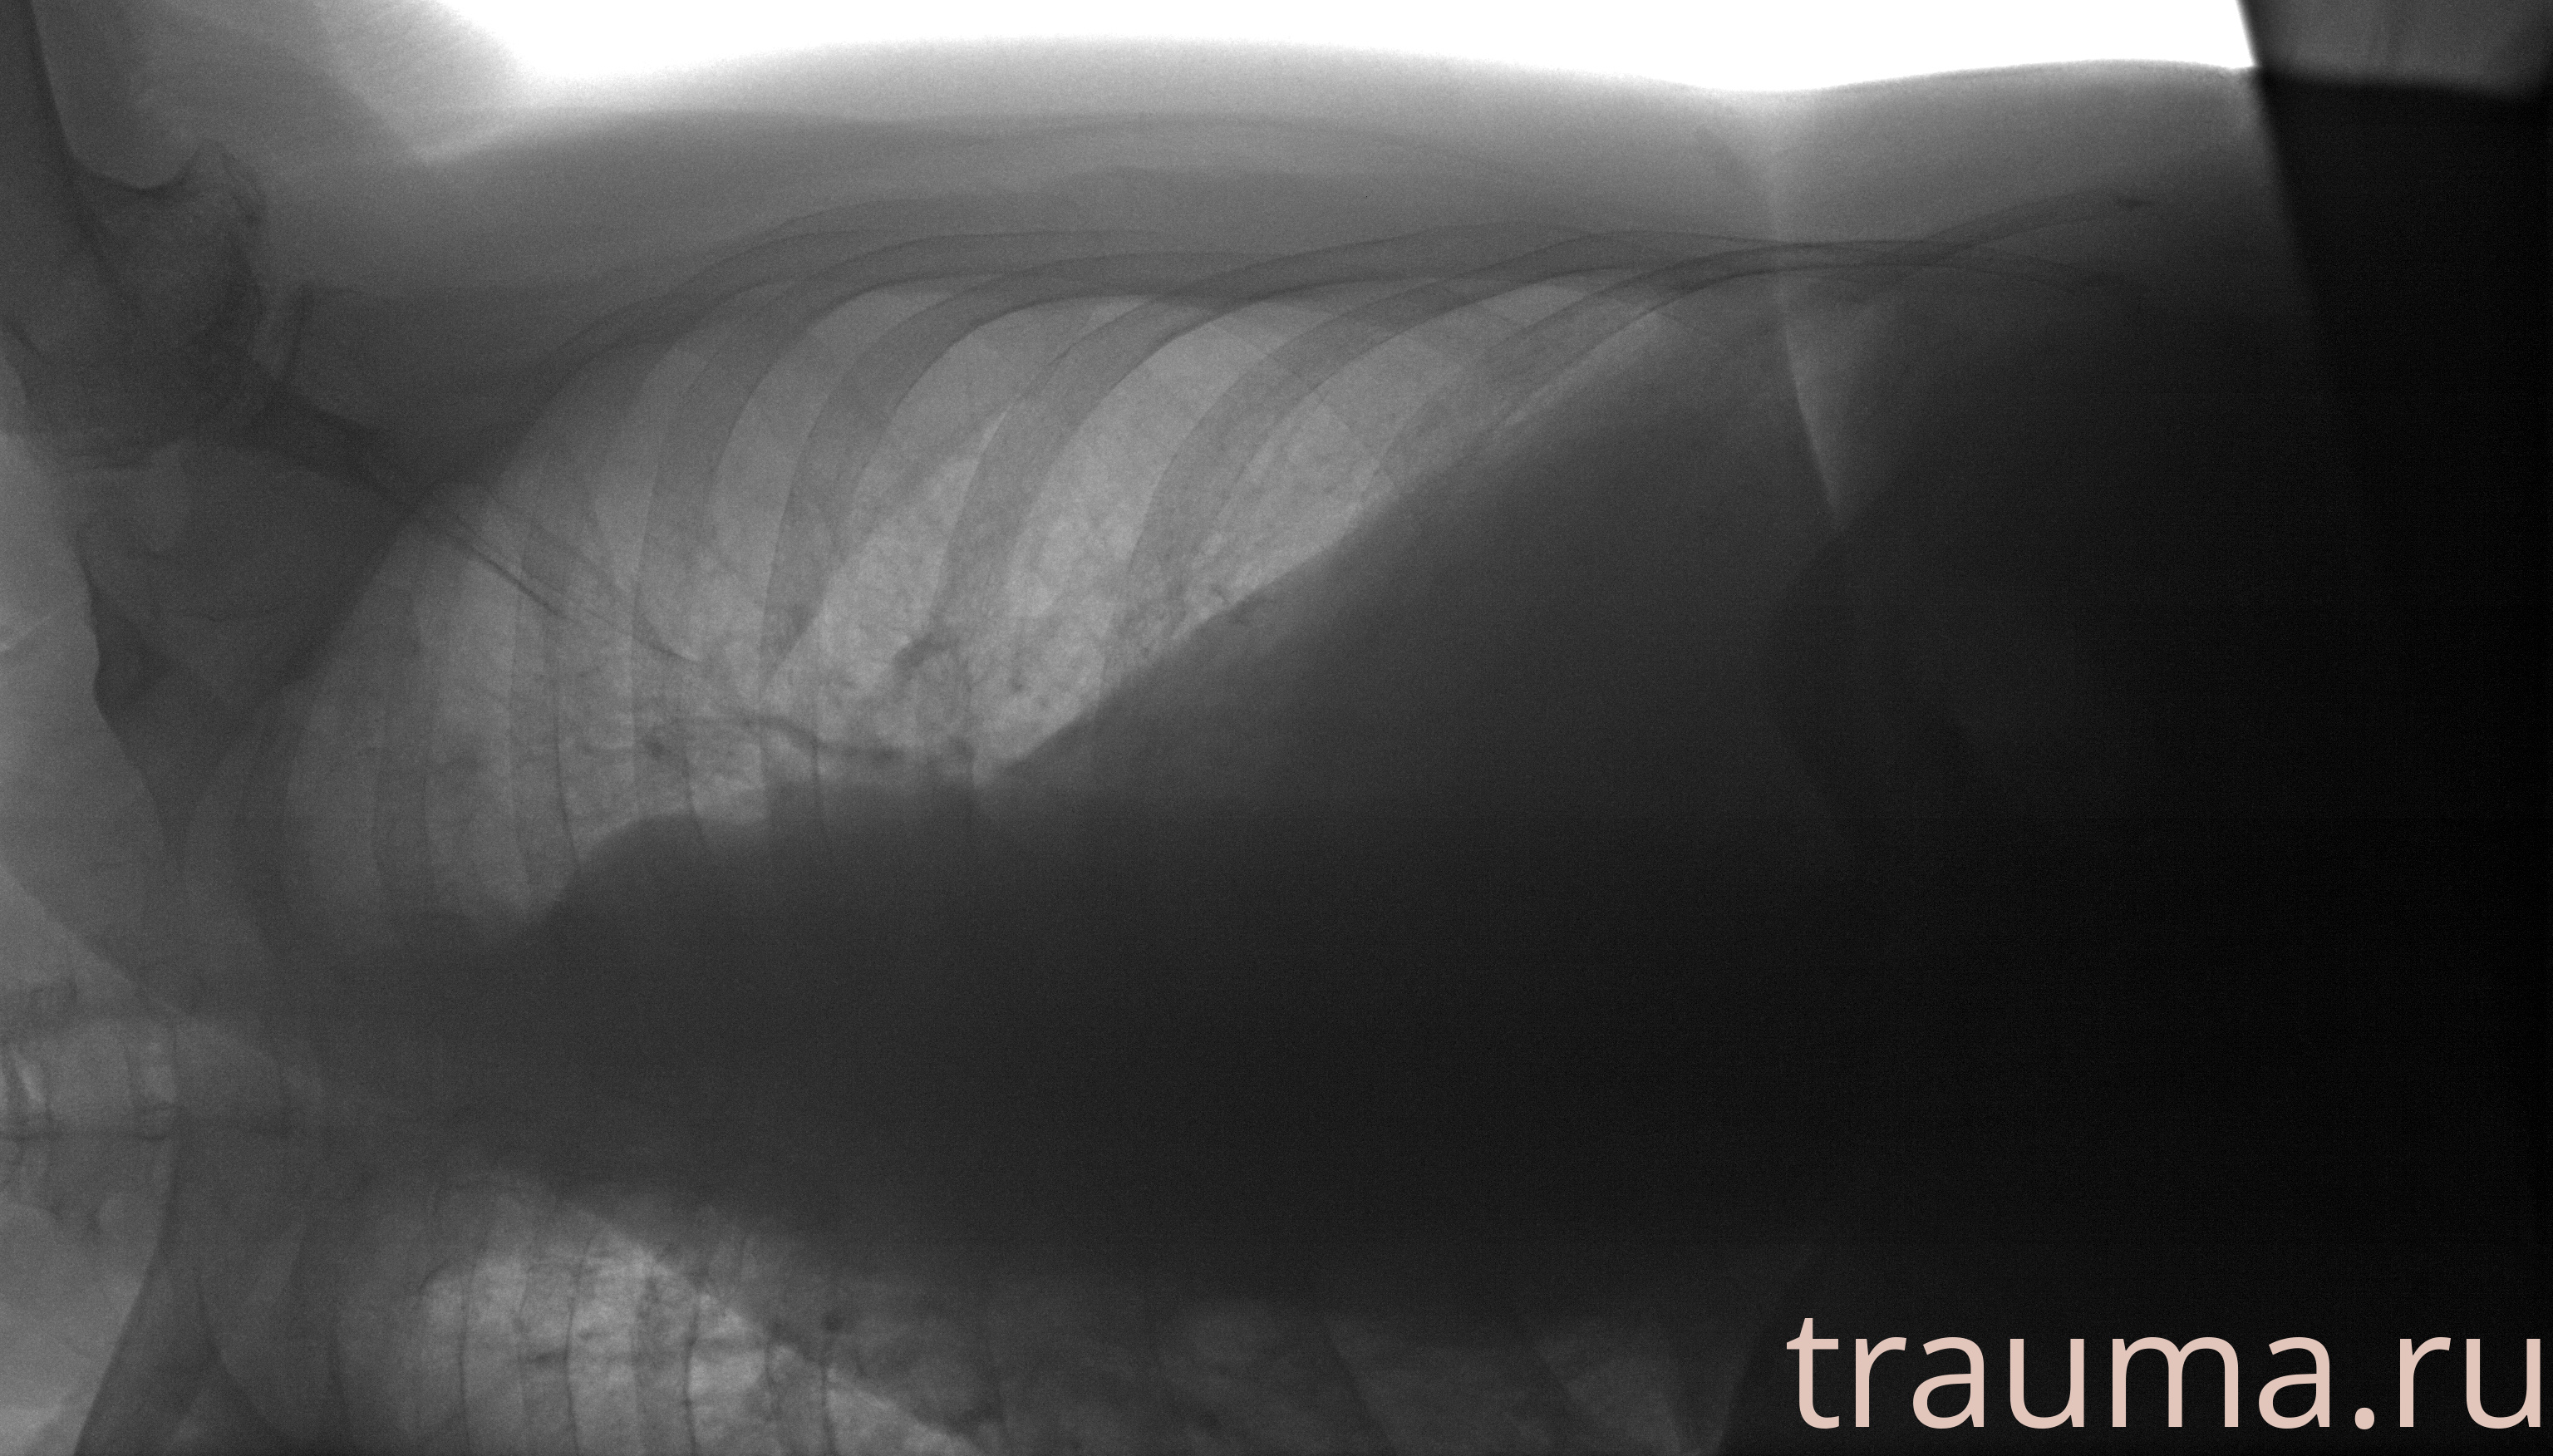

Рентген на дому: по вашему адресу приезжает врач-рентгенолог, травматолог-ортопед с мобильным рентгеновским аппаратом, проводит диагностику травмы или заболевания, делает необходимые рентгенограммы, дает рекомендации по дальнейшему лечению. Получить качественные снимки в домашних условиях возможно благодаря уникальной методике, разработанной МосРентген Центром для института  Склифосовского

при переломе шейки бедра и пневмонии от компании МосРентген Центр - партнера Института имени Склифосовского